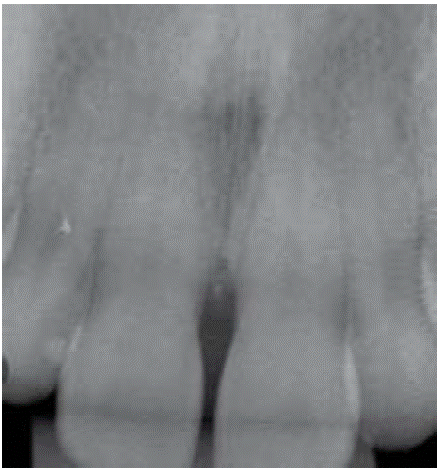

Clinical examination revealed an inflammatory gingival lesion at the level of teeth 3.4 and 3.5. Measuring approximately 15x9 mm. The lesion covered the vestibular side of the clinical crown, it was firm, lobulated, of rugged texture and bleeding upon stimulus (Figures 1and2). Periodontal assessment did not reveal periodontal pockets; presence of plaque was observed, and an O'Leary oral hygiene index of 18.75 was determined. Radiographic evaluation revealed absence of interproximal contact between teeth 3.4 and 3.5 as well as restorative material in the interproximal area (Figure 3).

Figure 3 Periapical X-ray of the lesion area. Absence of interproximal contact between teeth 3.4 and 3.5.

Radiographic examination revealed bone crest alteration between teeth 1.1 and 2.1 (Figure 10).